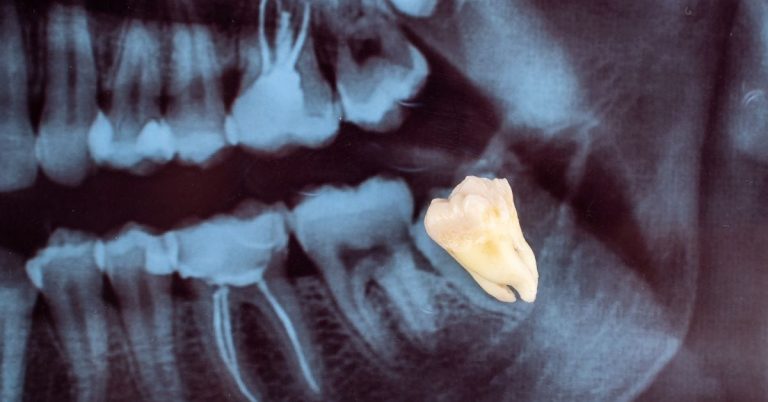

अक्ल दाढ़, जिसे अंग्रेजी में विजडम टूथ भी कहा जाता है,मुंह के ठीक पीछे के हिस्से में मोलर का तीसरा सेट होता है। आमतौर पर अक्ल दाढ़ वाले दांत व्यक्ति के 17 से 25 वर्ष की उम्र के बीच आते हैं। इन दांतों के आने पर व्यक्ति के मसूड़ों में सूजन, दांतों में दर्द और...